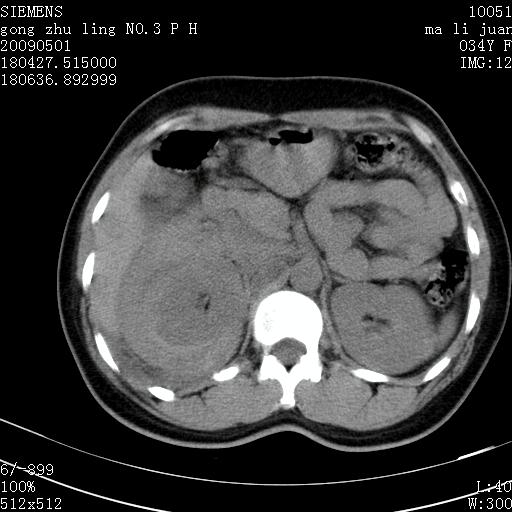

标题: CT19733:右肾碎裂

青年女性,骑摩托车摔伤。

右肾碎裂伤,包膜下血肿。

术中仅见右肾碎裂,肾蒂血管未见断裂。

支持 右肾破裂伴肾包膜下及肾周血肿。

右肾破裂并右侧腹膜后间隙出血。